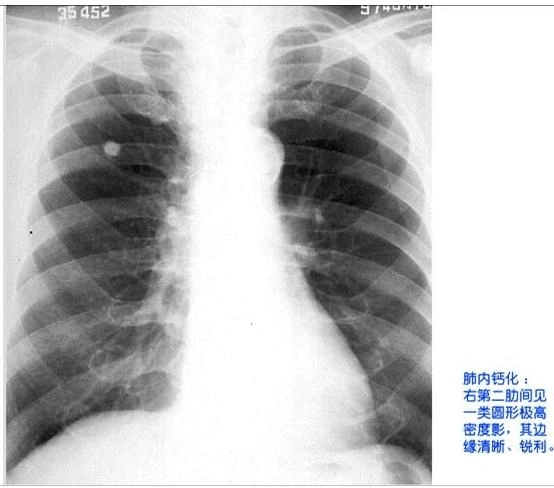

肺内钙化病灶的鉴别诊断

4种常见钙化灶和影像学说明!

肺部点状钙化影是什么意思肺部点状钙化灶肺部点状结节肺部点状致密影

肺内多发钙化灶考虑什么

肺内钙化灶